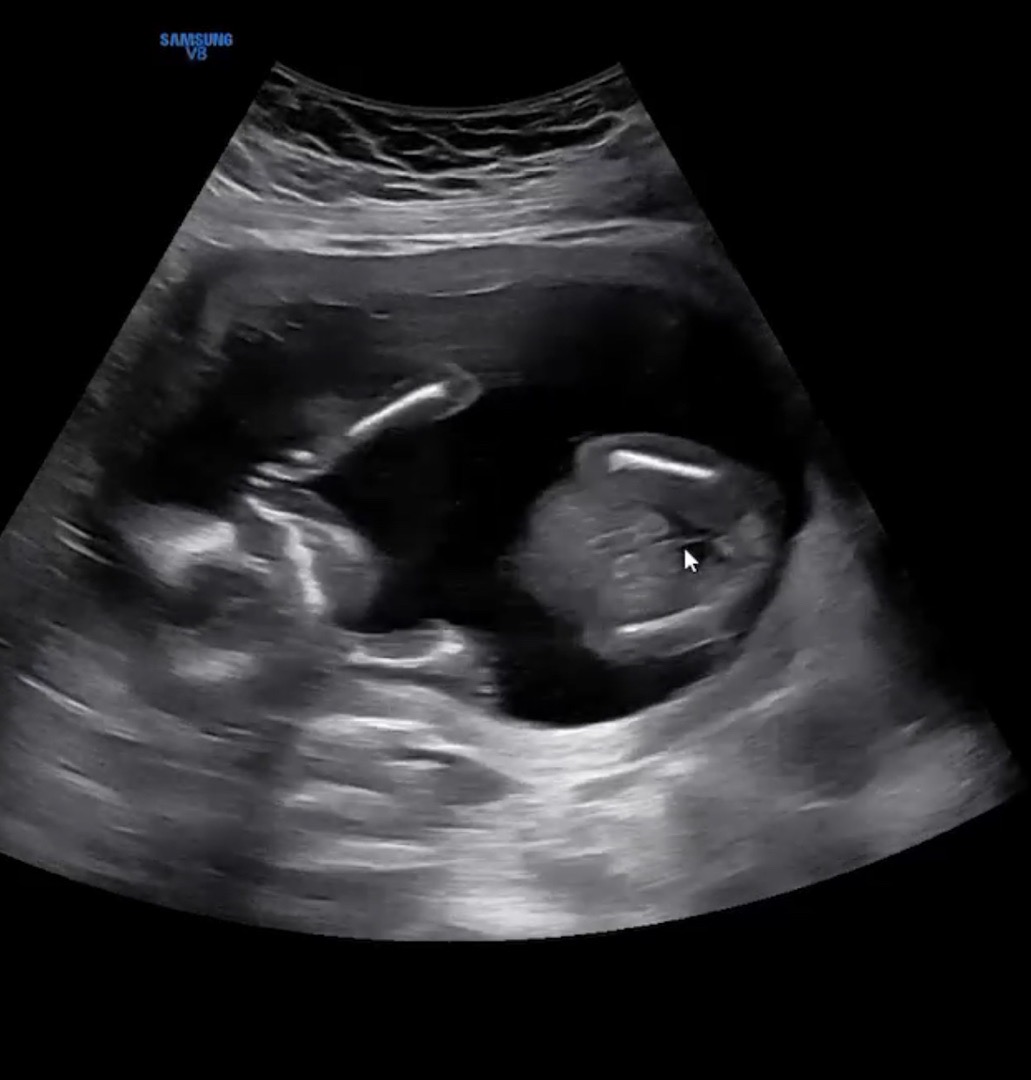

16주 4일차 성별반전있을까요?

70프로 딸일꺼 같다고 들었어요! 반전있을까요?

저도 16주 3일인데 70프로 딸일 것 같다는데 혹시 몰라서 아직 확신을 못하겠어요....